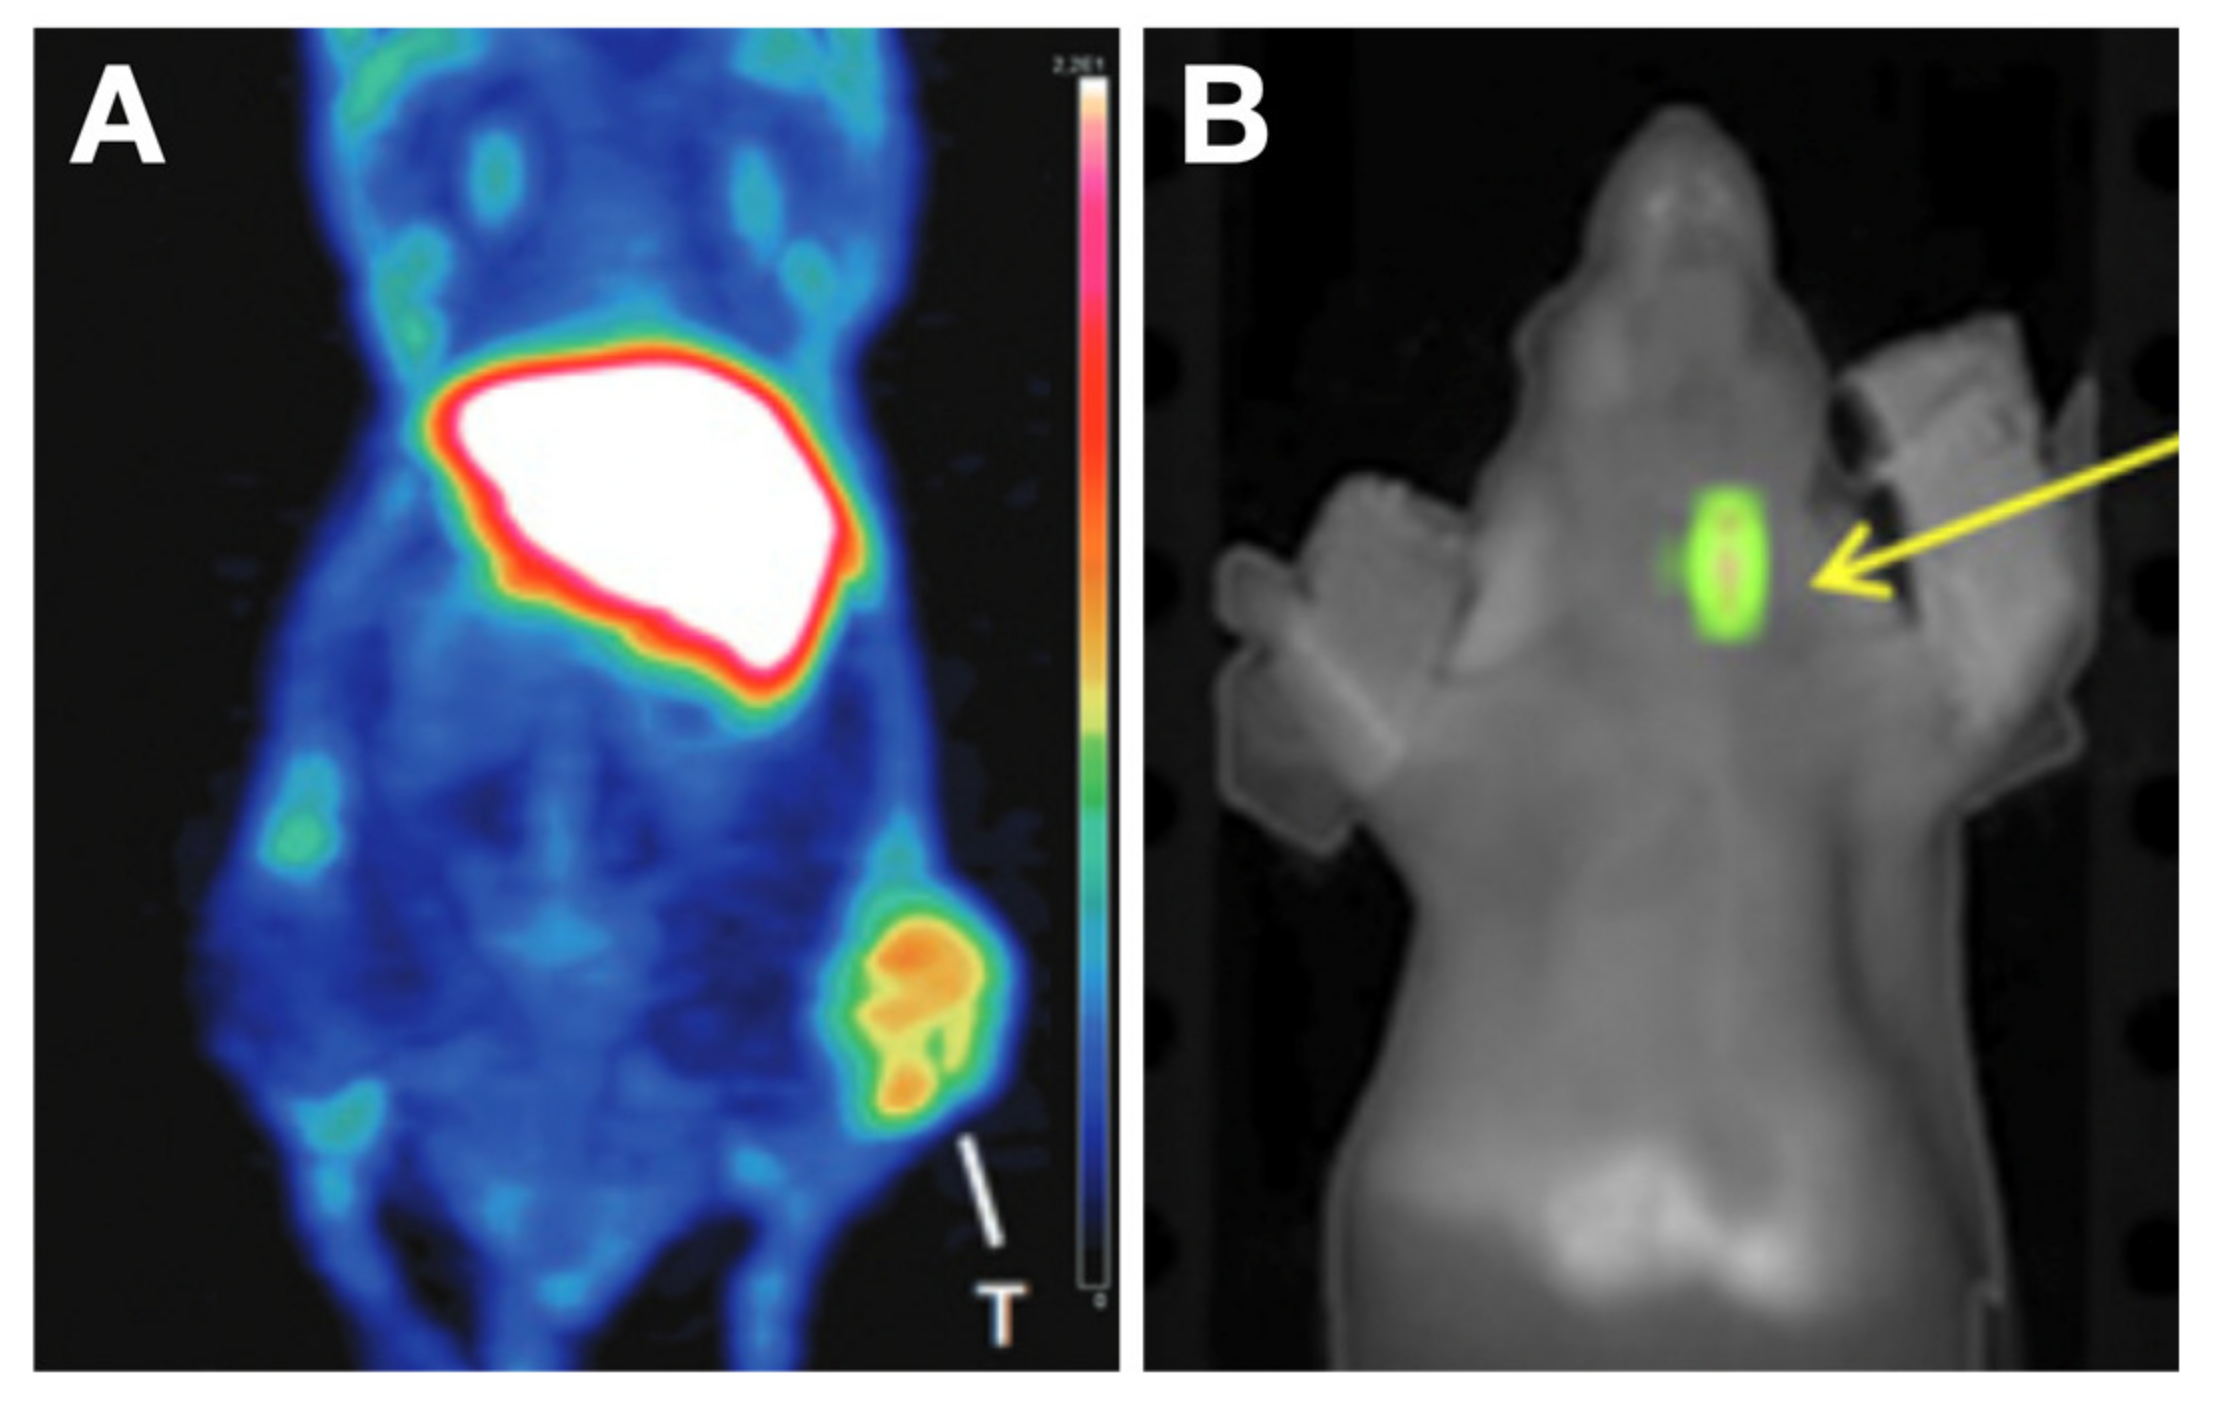

5.1.1. Prominin 1 (PROM1, CD133)-Targeting Probes

5.1.2. PTC Tissue-Targeting Probes